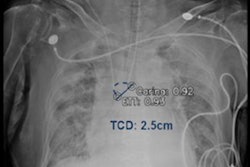

Process to estimate optimal depth of endotracheal tube using machine-learning model. (A) Acquire the recorded value of (a) fixed endotracheal tube depth from the electronic medical record and measure the distance from the carina to the tracheal tube tip (b) on the chest x-ray. Then, assume that the median of the distance from the carina to the upper margin of T1 and the distance from the carina to the lower margin of T3 is the optimal tracheal tube tip position (o). Finally, the ETT optimal depth value is derived by moving (a) as much as the distance that (b) has moved to the position of (o). Image courtesy of Scientific Reports through CC BY 4.0.According to the findings, the rate of inappropriate ET location was significantly lower using the machine-learning model (17.9%) compared with formula-based methods (35.7%, 62.2%, and 46.6%), the researchers reported.